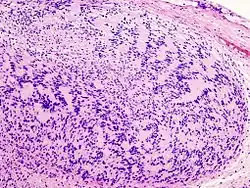

Guz zbudowany jest z jednorodnych komórek o morfologii komórek Schwanna. Jądra komórkowe są wydłużone, układają się w wiry, pasma lub palisady. Charakterystyczne dla guza jest tworzenie tzw. ciałek Verocaya. W części przypadków wraz ze wzrostem gęstości komórkowej jądra przyjmują okrągły lub wieloboczny kształt. Typ histologiczny w którym komórki są zbite i ustawione palisadowato określa się jako Antoni A; typ w którym komórki są ułożone nieregularnie i luźno to typ Antoni B.